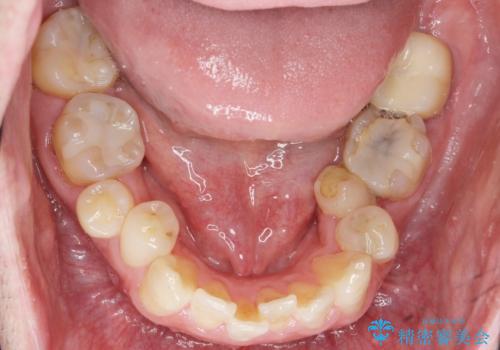

- 下の奥歯が内側に生えていることを主訴に来院された患者様です。

精査したところ、左下の小臼歯(左下5)が舌側転位しており、また隣の歯の詰め物は欠け虫歯になっていました。

矯正は絶対にしたくないという強いご希望により、舌側転位している歯を抜去し歯肉の治癒を待ったのち、両隣の歯の補綴治療を行いました。